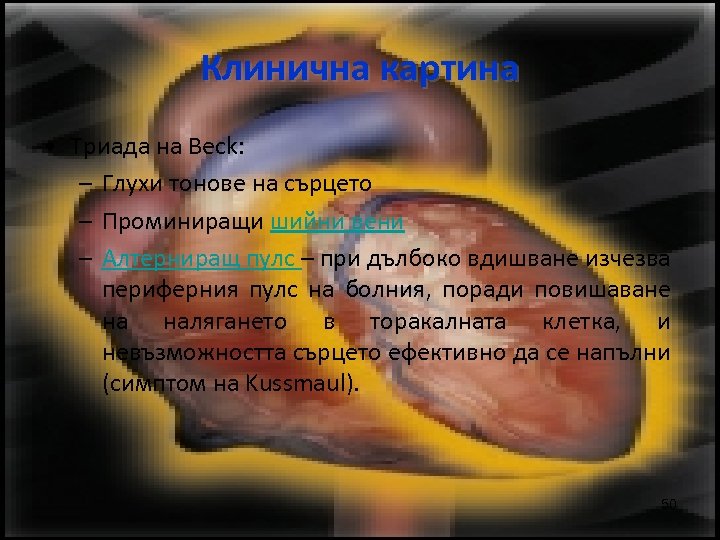

Клинична картина • Триада на Beck: – Глухи тонове на сърцето – Проминиращи шийни вени – Алтерниращ пулс – при дълбоко вдишване изчезва периферния пулс на болния, поради повишаване на налягането в торакалната клетка, и невъзможността сърцето ефективно да се напълни (симптом на Kussmaul). 50